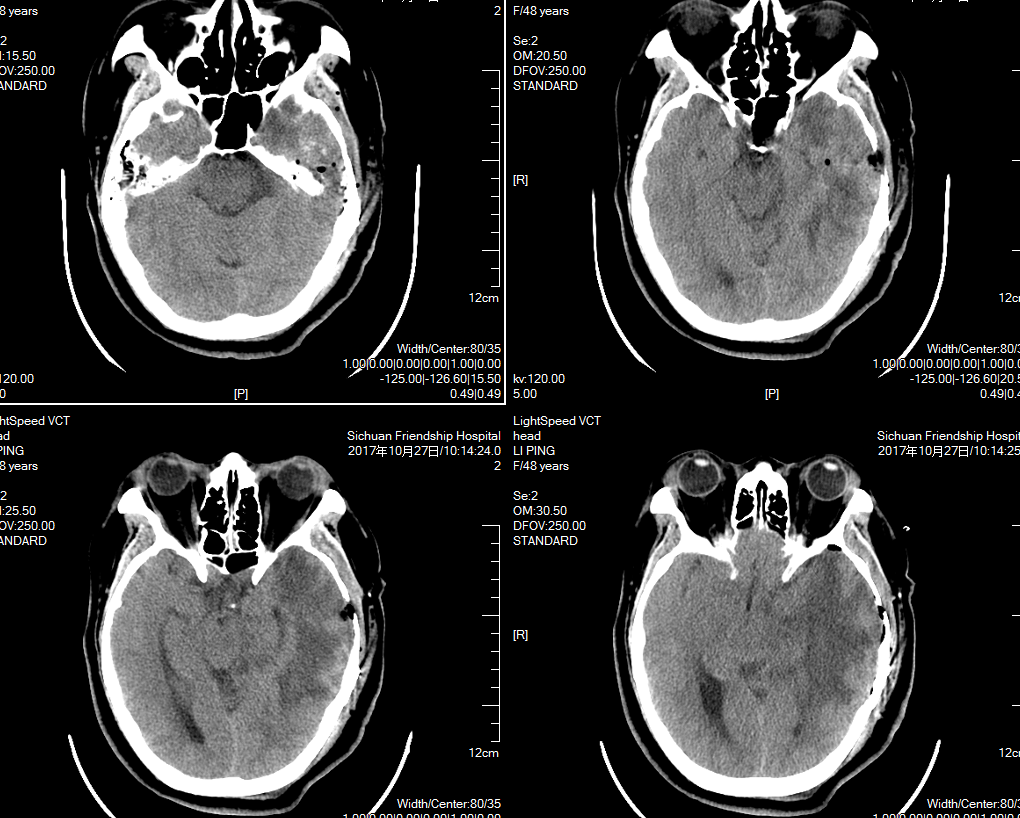

术前头颅ct术前mri术后头颅ct术后病理报告证实为脑胶质瘤.

图片尺寸1158x549